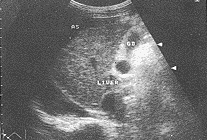

肝内回声改变:肝内回声不均匀,光点粗大,呈高、低不等弥漫小结节回声分布,以高回声为主,类似于“球状”(图2)。大小在3cm以下,极少超过5cm。无包膜。无明显晕环。很少见到融合成片。后方有轻度衰减现象。正常肝组织不易探及。若病变早期局限于某一肝叶段,其它肝叶组织可正常。肝内回声改变与肝硬化(图3)不同。

图2 弥漫性肝癌

图3 肝硬化

肝脏体积呈弥漫性增大,肝右叶上下径线多>14cm。肝包膜呈凹凸不平、波浪状改变,较圆钝。肝内回声结构紊乱,呈高、低回声不均匀分布。光点粗大,多呈弥漫分布高回声小结节,类似于“球状”,无包膜,无明显声晕。结节大小以3cm以下为主,极少超过5cm。很少见到融合成片,但后方多有轻度衰减现象。有时病变局限于某个肝叶段,而致肝脏形态不规则。肝内静脉变细,门脉管系走向均显示不清,并见血管绕行及中断现象。门脉主干直径>1.4cm以上,多伴有栓子形成。是诊断弥漫性肝癌的重要依据〔3、4〕。正常肝组织不易探及。若病变局限于某一肝叶段,其它肝叶组织可正常。同时伴有腹水、脾肿大、胆囊的改变。